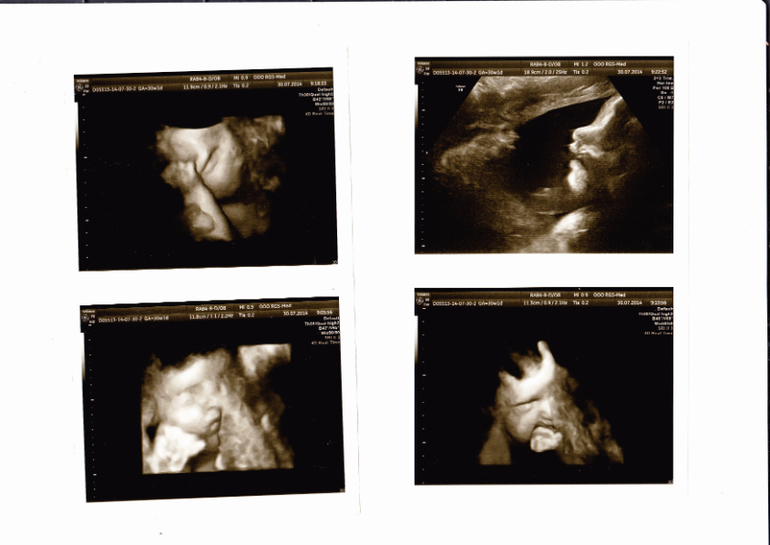

,(парочку фото прилагаю)сходила на плановое УЗИ(взяла и фото и видео сыночка),сходила на прием,получила на руки и родовой сертификат и подарок от "Pampers",и больничный.Уже все отдала в бухгалтерию(кроме памперса конечно)))),буду ждать декретные и зарплату))))На УЗИ сказали,что развиваемся мы отлично,как в аптеке,все по граммам и мм))))ттт,чтоб не сглазить,сыночек уже весит 1747гр,получается с 25.06 сынуля набрал уже 900 гр,нам 30 неделек и 1 день было по М,а по данным узи немножко опережаем.Индекс околоплодных вод 18,5,тоже норма,водичка чистая,хорошая без взвесей))))Есть небольшое обвитие,но сказала врач,что это нормальное явление для такого срока,и малышок еще тысячу раз перевернется)))Он у меня повернулся уже головушкой вниз,как и положено,но все равно умудряется толкаться сразу в обе стороны живота одновременно)))Ножка (стопа)у сыночка уже целых 6 см!!!

Футболист)))Не захотел в этот раз показывать личико,то одной ручкой закрывал,то другой кулачок в ротик пытался засунуть,отворачивался и ни в какую,а в конце вообще язык показал и спрятался,но это мы уже не в 3д,а в простом узи изображении рассмотрели)))ПДР ставят на 1 октября(было 7ое),сказали примерно в середине сентября уже ложится в роддом на ПКС(я сама так хочу,да и первые роды тоже были КС)Вес уже 74,5 это получается +17 кг